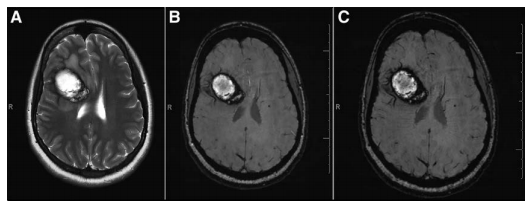

脑海绵状血管瘤(CCM)或海绵状血管畸形是结构异常的慢血流毛细血管的集合,主要位于中枢神经系统。这些是多个桑椹样扩张的毛细血管空洞,没有正常的脑实质结构。通常,个别海绵状血管瘤被含铁血黄素所包围,这是由于毛细血管异常而导致的远处渗出。据报道,CCMs是继发育性静脉畸形(DVA)之后的二大中枢神经系统血管畸形,多数CCM病例都是由单个病变合并或不伴有DVA组成。这些被称为散发性脑海绵状血管瘤,通常无症状和非遗传性。由遗传性或遗传性突变引起的多发性遗传性病变称为家族性脑海绵状血管瘤FCCM。CCM可见于中枢神经系统的多个部位,幕上病变比幕下病变更常见病变。

脑海绵状血管瘤CCM患者复发性微出血导致含铁血黄素沉积,病灶周围出现胶质增生和炎症,被认为是CCM患者癫痫发作的原因。与一般人群相比,CCM患者一次发作后再次发作的风险相对较高。病变部位和数量似乎与出血风险相关;幕下较深的病变比幕上病变的风险更高,多发病灶也与出血风险增加相关。研究报告称,在样本人群中,每年的脑出血风险为1.6%至4.6%,估计每年每个病变的脑出血风险为0.1%至1.4%。据估计,CCM患者5年内发生脑出血的风险为15.8%,复发性脑出血的年风险随着时间的推移而降低今年是临床上一个重要的因素,它是决定CCM患者正确治疗策略时考虑的因素。CCM患者未来再出血的2个主要危险因素是脑出血的一次发作和脑干病变(危险比分别为5.6和4.4)。另一项研究发现,CCM引起的出血较重要的评估因素是先前的出血。如果不进行治疗,脑干CCMs的出血率会高出2%到60%,并且在治疗时也会因并发症导致死亡外科手术。其他因素包括女性,海绵状血管瘤的大小和数量。虽然年龄似乎没有影响,但脑出血的发生和终生出血风险的增加在年轻的FCCM患者中被发现。一项对西班牙裔FCCM患者的研究发现肥胖患者与较少的损伤有统计学意义的联系,老年患者发生多发性病变的风险增加,高血压不是多发性病变的危险因素。